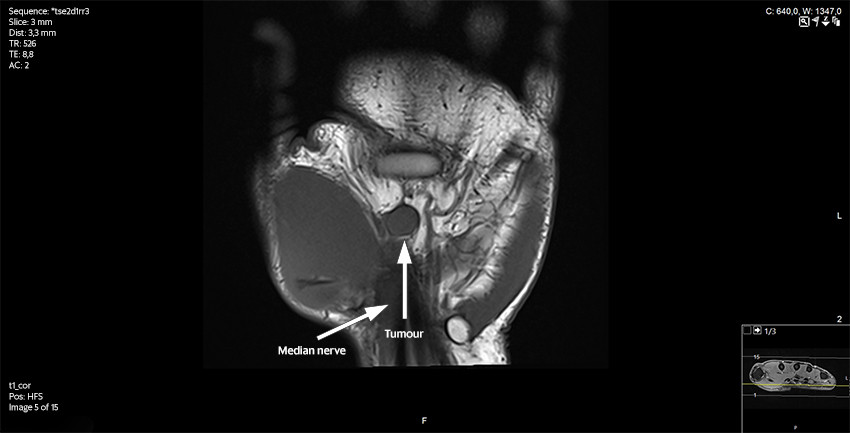

The patient was then referred for an MRI scan at a private clinic and subsequently to the orthopaedic department at the regional hospital. Following the MRI scan, the radiologist reported a contrast-enhancing, well-defined soft tissue tumour adjacent to or on the median nerve at the outlet of the carpal tunnel. It was concluded that the tumour was consistent with a schwannoma, but that another type of tumour could not be ruled out (Figures 2 and 3).

The patient was immediately informed about the biopsy result and referred to a sarcoma centre. The preoperative images from the MRI scan were re-assessed by radiation oncologists. They concluded that there was a solid vascularised tumour along the median nerve with no typical 'target sign' or 'fascicular sign' as often seen in benign nerve sheath tumours. It was not possible to make a more precise diagnosis on the basis of the preoperative MRI images. Chest CT, abdominal CT and ultrasound of axillary nodes revealed no signs of metastases. A repeat MRI scan of the hand showed no residual tumour. Due to the tumour's location adjacent to a major nerve and tendons, an expanded resection was not advised. The patient received postoperative radiotherapy, 2 Gy × 30, to reduce the risk of local recurrence. At the next follow-up, the wounds had healed following the radiotherapy. The patient had no nerve pain or neurological deficit.